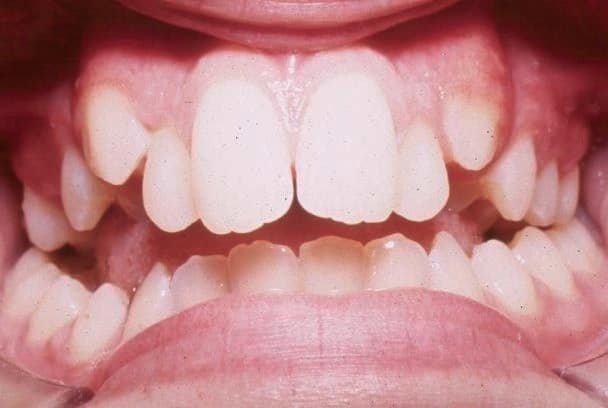

Zgryz krzyżowy to wada zgryzu, w której dolne zęby lub dolna szczęka wysuwają się na zewnątrz poza górne – ale w kierunku bocznym, nie do przodu. Prawidłowo, przy zamkniętych zębach, górne zęby boczne powinny zachodzić na zewnątrz na dolne. Przy zgryzie krzyżowym ta relacja jest odwrócona: dolne zęby boczne stoją na zewnątrz, górne wewnątrz.

Zgryz krzyżowy przedni to rzadziej spotykana odmiana, w której dolne siekacze stoją z przodu względem górnych przy prawidłowej lub cofniętej szczęce – różni się od przodozgryzu tym, że dotyczy tylko części zębów, nie całego łuku.

Zgryz krzyżowy to wada, w której dolne zęby boczne lub dolna szczęka wypadają na zewnątrz poza górne w kierunku bocznym. Prawidłowo górne zęby boczne powinny zachodzić na zewnątrz na dolne – przy zgryzie krzyżowym jest odwrotnie. Objawem jest zgryz boczny odwrócony widoczny przy szerokim uśmiech u lub przy badaniu zgryzowym. Przy jednostronnym zgryzie krzyżowym żuchwa często ucieka w bok przy zamykaniu – to bardzo charakterystyczny objaw. Ostateczne rozpoznanie stawia ortodonta na podstawie badania klinicznego i diagnostyki.